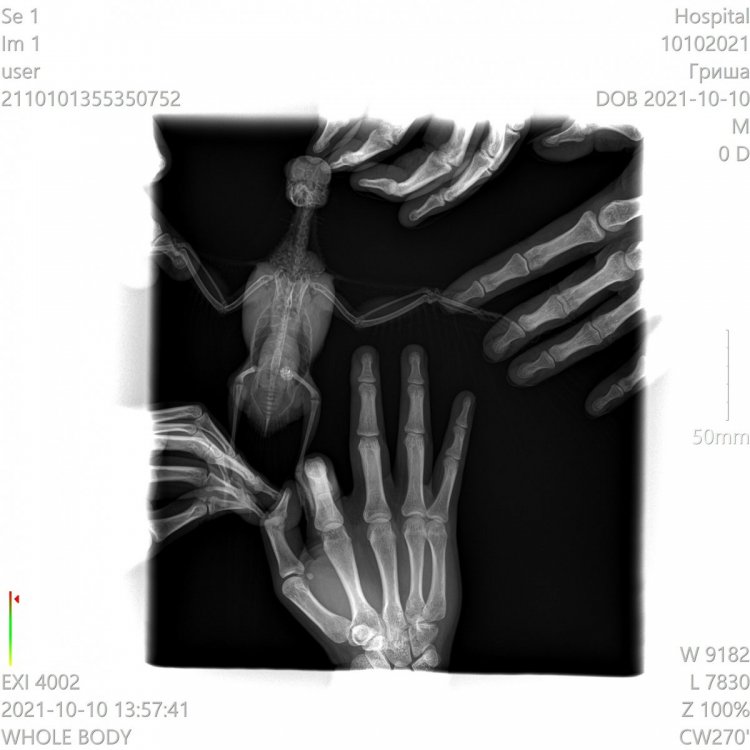

Здравствуйте! Лечу двух Гуленек - Оксаночку и Федорушку. Оксана у меня с конца июля. Лечили трихомоноз и микоплазму (не по анализам, а по симптомам, не сразу поняли, что это). Орнидазол 10 дней, пимафуцин на протяжении всего лечения + 4 дня, амоксиклав 10 дней, сумамед 14 дней. Все симптомы ушли во время лечения сумамедом. Изначально она попала ко мне с закисшими отёкшими глазками (пёрышки все были чистенькие) и слизью в горле, был запах от помёта (поэтому, возможно ошибочно, я и предположила трихомоноз) ,не всегда могла пищать, были приступы глотательных движений, во время которых слизь подступала к горлу и носу. Глазки стали проходить на амоксиклаве, но не до конца. На сумамеде всё ушло. Сейчас у Оксаночки,ттт, никаких симптомов нет. Федора у меня с 10 сентября, были наросты в горле, похожие на ранки, фото прилагаю, голоса не было, потом запах от помёта, лечила орнидазолом 14 дней, пимафуцин 14 дней. Думала голос восстанавливается, он стал лучше, но до конца не восстановился. Кроме того, когда полетает чуть больше чем пару тройку перелётов по комнате (когда мне ей лекарство надо дать, например) у неё отдышка. Дышит некоторое время с открытым клювом. Потом всё нормально, горлышко красное рыхлое. Периодически издаёт негромкий звук -пыф (как отрыжка).Бывало, кушает-кушает, потом шею вытягивает и некоторые зёрнышки вылетают. А по-началу вообще кушать трудно было ещё и из-за наростов, раздувалась вся. Наросты отпали, остальные симптомы до конца не прошли, поэтому поехали к доктору. Оксаночку даже брать не планировала, только в последний день решилась. В итоге ей, послушав обеих птиц, врач сделала рентген Оксаночке (фото прилагаю). У неё прослушались сухие хрипы с одной стороны, и жёсткое дыхание с другой. У Федоры жесткое дыхание с одной стороны, рентген не делали. Обеих пшикнули Фипристом 1 раз на кожу.Лечение тоже выписали одинаковое:1.Доксициклин (доксифин) 100мг растворить в 5мл воды,давать по 0,3мл (Оксаночке 0,28мл) внутрь - 2 раза в сутки,21 день2. Толтарокс 5% 0.15 мл (Оксане 0.14мл) внутрь 1 раз в сутки, 5 дней3.Дирофен 20 (паста или суспензия) 0,3мл внутрь, 1 раз в сутки, 3 дня4. Нистатин только Оксане прописали, но сказали, что и Федоре я могу его давать. Доктор сказала, что он транзитный, на печень не влияет,а пимафуцин не работает. На доксициклин у Оксаночки была реакция (видео прилагаю, если приложится). Спрыгнула слизь с кровью, это не симптом, такого не до не после (ттт) не было, а именно реакция на препарат. Его обеим поменяли да ципрофлоксацин. Таблетки 500мг, 1/2табл растворить в 6мл воды, 0,26 мл Оксане (она весит 280 грамм), 0,3мл Федоре (она весит 300 грамм), 2 раза в сутки Противопаразитарные на третий день (тоже обеим) отменили, т.к. Федорушку тошнило из-за них. В один из разов когда тошнило Федору, она тоже вытошлила немного слизи. Нистатин у нас не продаётся, даю Флуканозол. Капсула 50мл /5 мл воды, по 0,3 мл /2 раза в день. Сегодня 5й полный день приёма ципрофлоксацина. У Оксаночки восковица была белая до начала лечения, после доксициклина и реакции на него - порозовела. Сейчас чуть менее розовая, но не белая. Видимых симптомов у Оксаны как не было, так и нет. Федорочка «пыфает», при полётах отдышка ещё есть, но кушать стала не вытягивая шею, зерна не разбрасывает. Купила стетофонендоскоп, хочу следить за динамикой, ничего не смогла услышать. Не подскажете, как им пользоваться? Может я что-то не так делаю? Рентген у Оксаночки сильно нехороший? Ципрофлоксацин у нас дозировки в пределах нормы? Просто я по форумам полистала, везде гораздо ниже они. Сдавали пцр на микоплазму (в горветлаб спб), делали неделю, результат -у обеих нашли микоплазму. Да, у Оксаночки ещё переломы, но изначально она ко мне попала в таком состоянии, что не до них было, а потом они уже схватились.